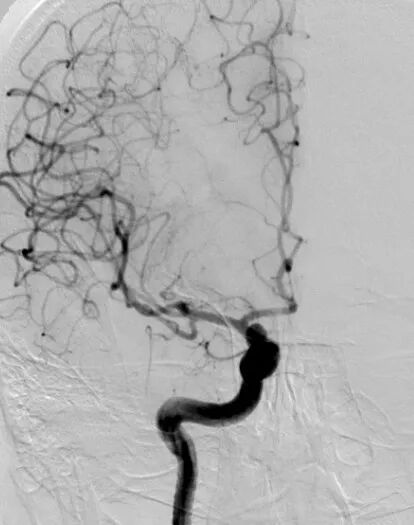

术前影像学检查CTA显示右侧颈内动脉海绵窦段巨大型动脉瘤。

术前3D显示右侧颈内动脉海绵窦段巨大型动脉瘤

DSA正位造影

动脉长鞘怎么置入深谋远路 | 千人皆翘首,万唤今始来——国内首款7F长鞘在血流导向密网支架联合弹簧圈栓塞治疗动脉瘤的首次应用_https://www.jmylbn.com_新闻资讯_第5张

DSA侧位造影